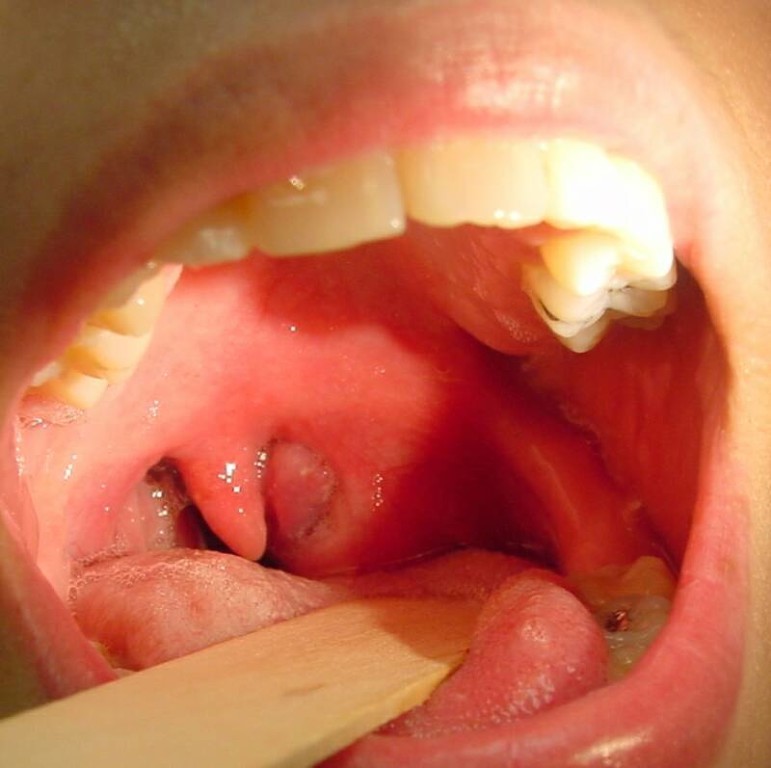

Клиническая симптоматика развивается довольно быстро. По локализации абсцессы принято делить на глубокие (в толще мышц) и поверхностные (чаще локализованные на спинке под слизистой). Поверхностные в отдельных ситуациях способны вскрываться самопроизвольно; после опорожнения гнойного очага быстро наступает облегчение состояния.

Для глубоких гнойников типичны такие клинические признаки, как гиперсаливация (обильное слюноотделение), цианотичный оттенок слизистой и присутствие налета грязно-серого цвета. Язык может распухнуть настолько, что не помещается в полости рта. В тяжелых случаях возникают проблемы с дыханием; при этом больной переживает страх смерти и занимает вынужденное (сидячее) положение.

В ходе визуального осмотра определяется гиперемированная отечная зона. При пальпации обнаруживается весьма болезненное уплотнение.